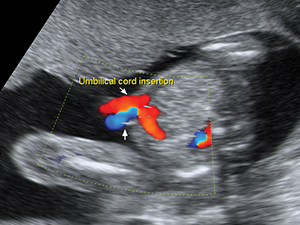

Abdomen